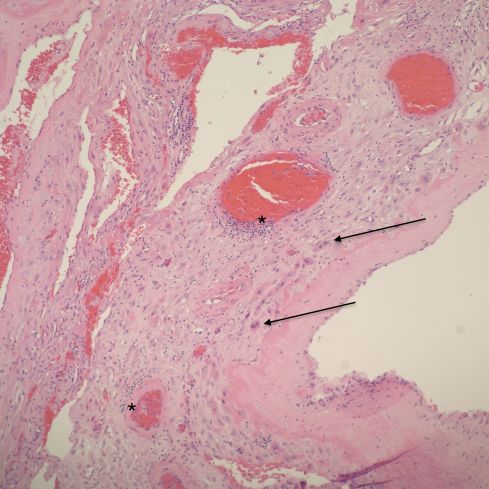

Fig 10a: This sample of parietal membrane demonstrates loss of the intact cytotrophoblast layer with many independent often multinucleated trophoblast cells (arrows). There are multiple profiles of a spiral artery. Some are normal, and others show dilatation, thinning and necrosis of the media and focal inflammation (*). H&E 10x

Fig 10b: This higher power of the area of the “*” in the previous figure shows the eosinophilic necrosis of the media, and the mononuclear inflammation. The red cells appear distorted suggesting stasis. H&E 40x